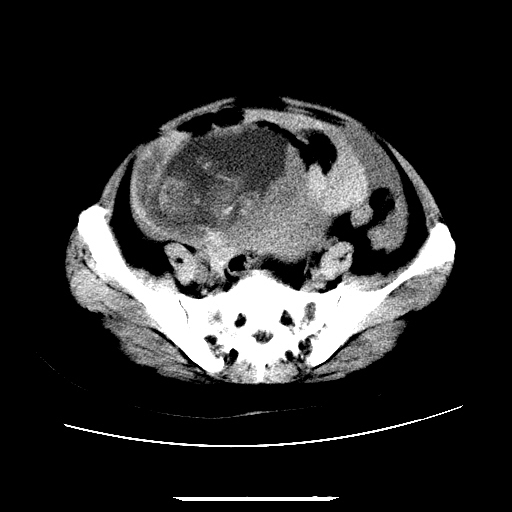

f,45y.怀孕4月晕倒,b超提示死胎,有手术结果,请展开讨论后明天告诉。

膈下-肠间隙内见气体密度影,子宫轮廓显示不清,宫腔-腹腔积液,首选考虑---子宫破裂出血。

1)宫腔妊娠。2)子宫破裂出血,腹腔及盆腔积血。

怀孕4个月晕倒,病史就这么简单?有没有腹痛呢?腹腔内有没有气体?窗宽太窄了脂肪组织与气体已不好分。如果有气体,那就是空腔脏器穿孔,如胃肠穿孔。如没有气体,就考虑子宫破裂或宫外孕破裂。正常怀孕子宫破裂很少见,有可能是宫外孕。极有可能是残角子宫怀孕破裂。腹腔怀孕破裂也有可能。

感谢同行们的高见。手术结果:子宫破裂出血。

我们的诊断是:腹、盆腔积液(考虑腹盆腔脏器破裂出血);宫腔妊娠。让人纳闷的是当时我们没有经验,现在回头看看分析:4月宫腔妊娠:1、洋膜囊不可能紧贴胎体这么小;2仔细看看子宫后壁肌层模糊不清;3腹、盆腔液体来源原因?4、45岁高龄妊娠有晕倒。由此可大胆诊断:宫腔妊娠子宫破裂出血。